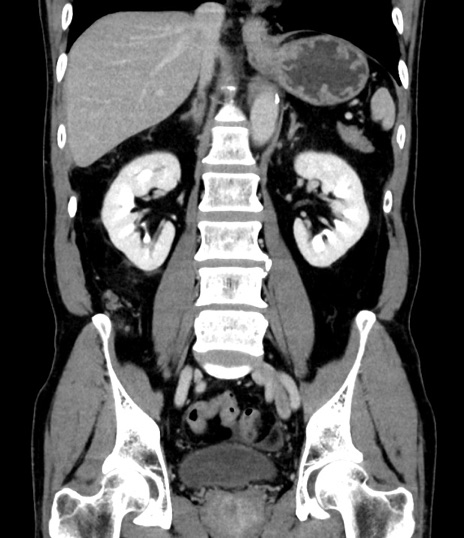

症例8(冠状断像)

【症例】 60歳代男性

【主訴】 黒色吐物

【現病歴】 4日前から嘔気自覚、2日前の朝食後にも嘔気あり、自分で手で嘔吐反射起こし嘔吐したところ血が混ざっていたため受診。

【既往歴】 5年前汎発性腹膜炎を伴う急性虫垂炎で手術、高血圧、前立腺肥大症、高脂血症

【身体所見】 腹部正中に手術癩痕あり 腹部平坦・軟圧痛なし膨満感あり

【データ】WBC 8400、CRP 4.54